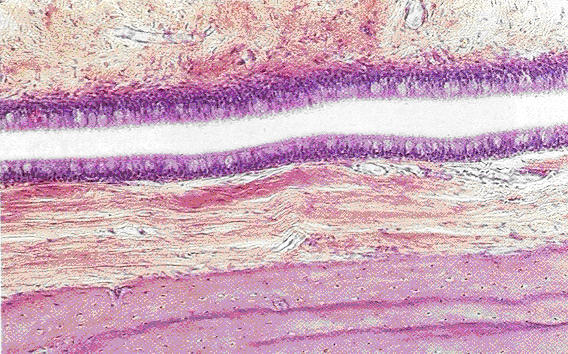

A very low magnification of the auditory canal (Eustachian canal) demonstrating the different structures.

Fig. 21.23 Auditory (Eustachian) canal

• Slit-shaped tube which is lined with pseudostratified columnar epithelium

• At its origin it is surrounded by bone which is then replaced with a J-shape cartilage ring

• Cartilage is partly hyaline and partly elastic

• Mixed glands and lymph follicles are found in the lamina propria